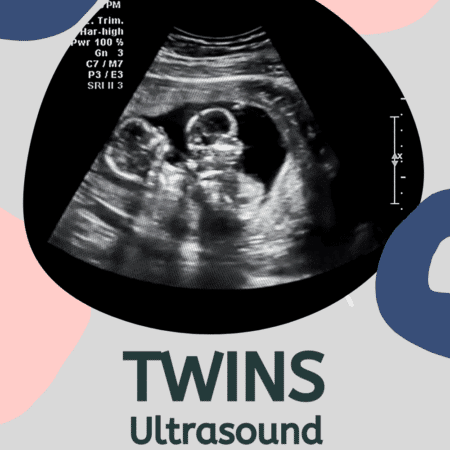

Imagine going for your 20-week ultrasound (halfway into your pregnancy), so excited to see your baby, and finding out that your baby is actually BABIES? It doesn’t happen super often, but sometimes a second baby goes undetected in early pregnancy. Most pregnant women find out its twins at their 8-week ultrasound, or even earlier. But see what twin moms had to say about finding out it was twins at a later ultrasound!

Let’s put it this way, nothing is truly impossible. It is highly unlikely that twins might go undetected. But, as you can see, it is certainly possible that you might have another little surprise in there and find out at a later ultrasound.

Do Twins Take Longer to Show Up On Ultrasound?

Again, it’s rare but possible to experience a “hidden twin” during your pregnancy. Mostly, the imaging available nowadays will pick up a second baby pretty early on. But a twin can be overlooked, especially if your provider isn’t looking for a twin at first glance.

How Late Can Twins Be Detected?

Twins will almost always be detected by your 20th week. It is unlikely you will even have to wait that long, but it can (and has) happened to many twin moms in our community. Beyond the 20 week mark, it is incredibly unlikely. But if you feel you are bigger than you should be or that something isn’t quite what you expected during your pregnancy, bring it up to your doctor.

When Do Twins Show up on Ultrasound?

Twins can typically be detected on ultrasound during the first trimester, usually around 6 to 8 weeks of gestation. In some cases, healthcare providers may be able to identify the presence of twins even earlier, especially with advanced ultrasound technology. The ability to visualize twins on an ultrasound depends on factors such as the clarity of the image, the position of the embryos, and the experience of the ultrasound technician.